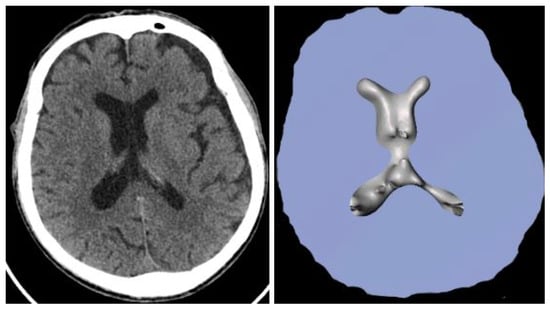

2.4.2. Segmentation

2.4.3. Model Creation and Visualization